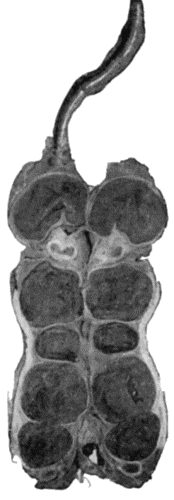

133.Skeleton of Rickety Dwarf 470

Dry cold obtained by means of icebags, or by Leiter's lead tubes through which a continuous stream of ice-cold water is kept flowing, is sometimes soothing to the patient, but when the vessels in the inflamed part are greatly congested its use is attended with considerable risk, as it not only contracts the arterioles supplying the part, but also diminishes the outflow of venous blood, and so may determine gangrene of tissues already devitalised.